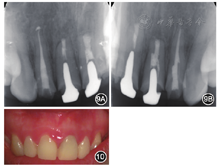

患者女性,23岁,于2014年5月就诊于北京大学口腔医学院·口腔医院牙体牙髓科。主诉上前牙牙龈肿痛,咬合痛半年。半年前曾因想改善前牙美观于外院行上前牙根管治疗及桩冠修复。1年前曾于北京大学口腔医学院·口腔医院正畸科就诊咨询。否认全身系统疾病,无药物过敏史。

临时冠修复体,龈缘红肿,

唇侧根尖区可见窦道口(图1)。去除临时冠后可见

可见白色氧化锆桩核,叩痛+~++,根尖区扪痛。

冠部唇侧开髓洞型可见牙色充填物,叩痛+,根尖区扪诊无不适。

探诊深度2~3 mm,无松动(图2)。

根管中部以上可见高密度桩核影像,根充欠填,

根尖有外吸收,根尖周低密度影。

根管中上段无明显显影,结合临床检查判断为纤维桩,根充欠填,根尖周未见明显低密度影(图3)。锥形束CT显示

根尖约4 mm×3 mm透影区,根尖部唇侧骨板缺损。

根尖可见约1 mm×2 mm透影区,唇侧骨板完整(图4)。